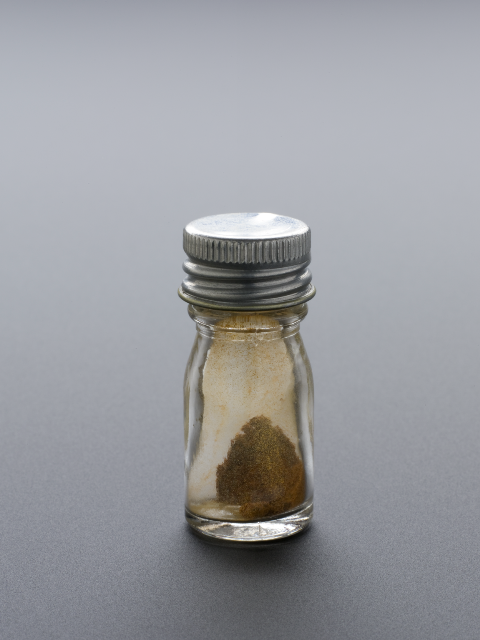

Laura Body from our Learning Support Team writes about one of her favourite Science Museum objects: a bottle of Penicillin